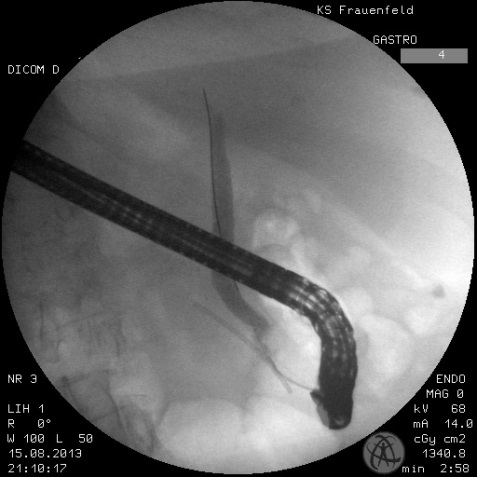

• ERCP = Endoskopisch retrograde Cholangiopankreatikographie: Sollten sich Steine im Gallengang (Choledocholithiasis) bestätigen, müssen diese Steine durch eine Spiegelung (endoskopisch) des Magens bzw. bis zum Eingang des Gallenganges in das Duodenum durch die Kolleginnen und Kollegen der Gastroenterologie entfernt werden.

Bild links: Cholangiographie: Mit Hilfe eines Bildverstärkers wird Kontrastmittel in den Gallengang injiziert, um die Gallengangsteine und Gallengangsanatomie darzustellen.